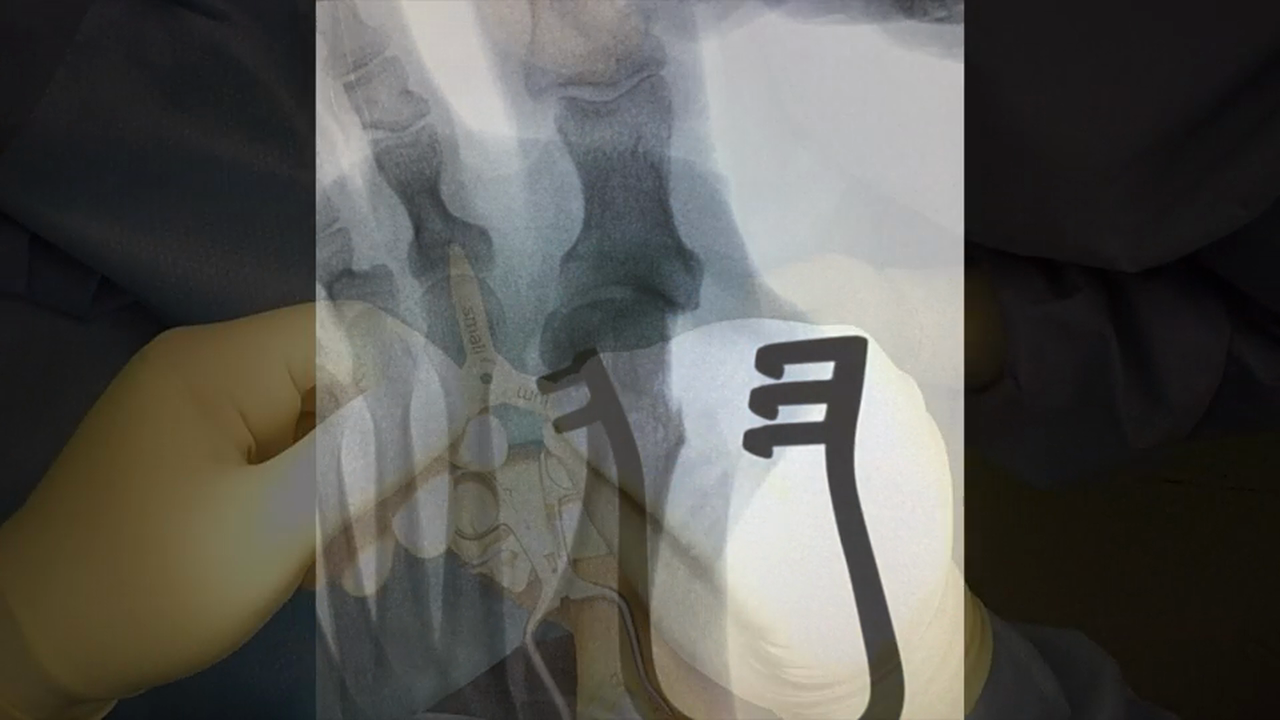

Hallux Valgus Correction

Hallux 2 w VO

Bunion ITS PLate w VO